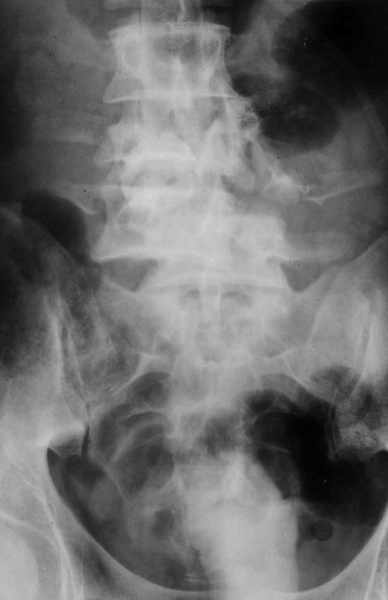

1

2

Высылаю рентгенограммы. Спасибо за рекомендации. Наша тактика согласуется с вашими рекомендациями за исключением транспедикулярной фиксации - у данного пациента на наш взгляд предпочтительнее наружная транспедикулярная фиксация (Курганский аппарат). Погружная конструкция предпологает одномоментную репозицию до выполнения забрюшинного доступа и ревизии переломов что теоретически может привести к повреждению дурального мешка и корешков. АВФ позволит восстановить ось позвоночника и смещение по длине непосредственно под контролем глаза на этапе внебрюшинного доступа. Сколько сегментов замыкать? Я думаю может потребоваться замкнуть и сегмент L2-L3. Предполагается использовать тело L4 для костной пластики таким образом, чтобы ширина спиномозгового канала на уровне оперированных сегментов была увеличена. Фиксация тел позвонков вентральной пластиной.